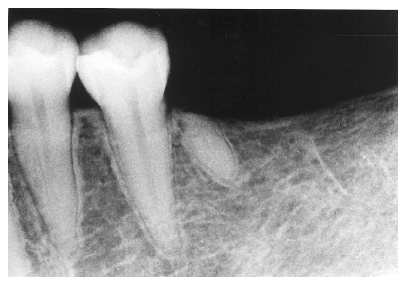

Apical Radicular Cyst

Epithelial remnants from tooth formation are always present as builder’s debris within the periodontium. These remnants can proliferate within an apical granuloma to form an apical radicular cyst, which can grow to several centimeters if left untreated. Apical radiolucencies greater than about six millimeters usually contain epithelial cyst material. Figure 14 illustrates a clearly defined apical periodontal cyst in a pulpless tooth following acute trauma.

If the process starts from a lateral, rather than an apical canal, a lateral radicular cyst can occur. Notice how the cystic formation in Figure 15 follows the lateral aspect of the tooth root, thus differentiating it from an apical cyst.

Figure 14 - Apical Periodontal Cyst

Figure 14

Figure 15 - Lateral Radicular Cyst

Figure 15